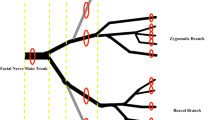

3.1 Fiber Teasing

Fiber teasing allows assessment of the pattern of nerve disease along several internodes of the same myelinated fiber. The most sensitive method for detecting segmental myelin changes, in principle, allows workers to determine whether these changes are primary or secondary to axon disease.

Dyck and colleagues provide the most comprehensive discussion of fiber teasing methodology and interpretation (Dyck et al. 1984; Dyck and Giannini 1993). We do not routinely employ nerve teasing in the assessment of biopsy specimens. Rather, we reserve this technique for special situations or research applications; some, but by no means all, workers share this approach (Logigian et al. 1994; Oh 1990; Schaumburg et al. 1992). Teasing is a difficult and tedious work and, as Dyck indicates, even an experienced technologist can prepare only 150–300 fibers a day (Dyck and Giannini 1993). Since the information gained from teased fiber examination is nonspecific, economic considerations mandate that diligent and experienced technologists may best utilize their energy in other areas.

When teasing is not performed properly, the information derived may be unreliable. Examining too few fibers risks drawing conclusions from a nonrepresentative sample. This result is especially likely when the technologist is not highly experienced and causes excessive fiber trauma, for even the most gentle teasing produces myelin artifact (Williams and Hall 1971). Large myelinated fibers are easiest to tease free, and as a result, a biased selection may thus be obtained. Dyck and colleagues have emphasized the need for appropriate sampling, suggesting that at least 100 fibers are necessary (Dyck and Giannini 1993). Assessment of demyelination “clustering” for deciding whether demyelination is primary or secondary requires at least five internodes per teased fiber. The literature, however, abounds with papers reporting results and even “normative data” based on as few as 20–50 teased fibers. Many papers even neglect to indicate how many fibers were studied.